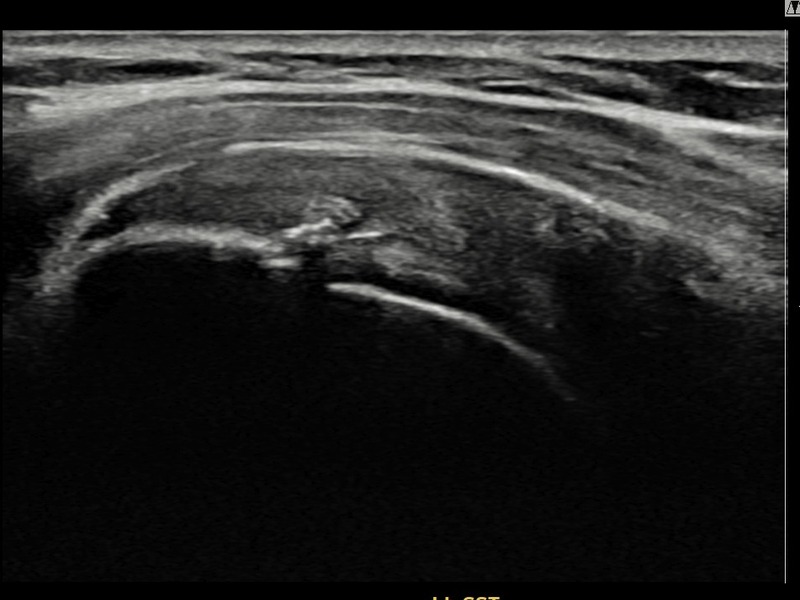

최ㅇㅇ님 · 우측 극상근건 점액낭면측 부분파열

우측 어깨 통증이 수개월간 지속되어 내원하셨습니다. 초음파 검사에서 점액낭면측 극상근건 부분파열이 확인되었으며, 어깨인대 축소봉합술 후 힘줄 두께가 회복되고 에코 연속성이 정상화되었습니다.